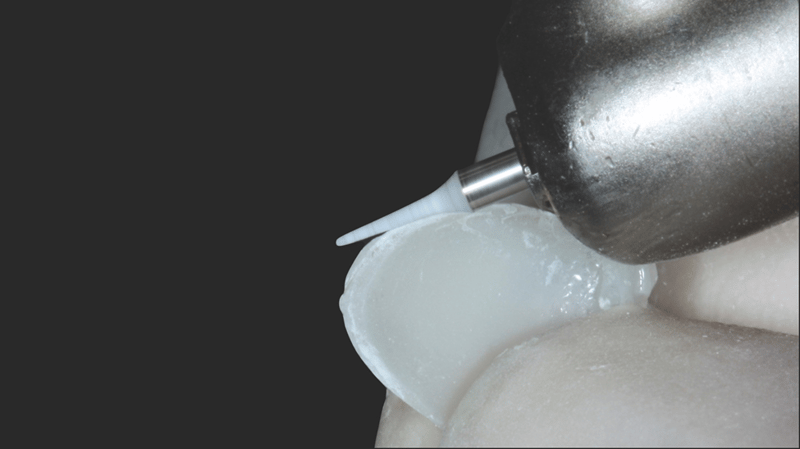

- Aanbrengen van de composiet: Transcend-composiet in de B1D-kleur werd aangebracht op 2/3 van de incisale rand, geleidelijk uitdunnend richting het gebied van de gingiva. In de buurt van het gingivale derde deel werd de Universal Body-kleur (UB) aangebracht. De restauratie werd verder afgewerkt met lagen Enamel White (EW) en een kleine hoeveelheid UB aan de gingivarand, voor een natuurlijke overgang.